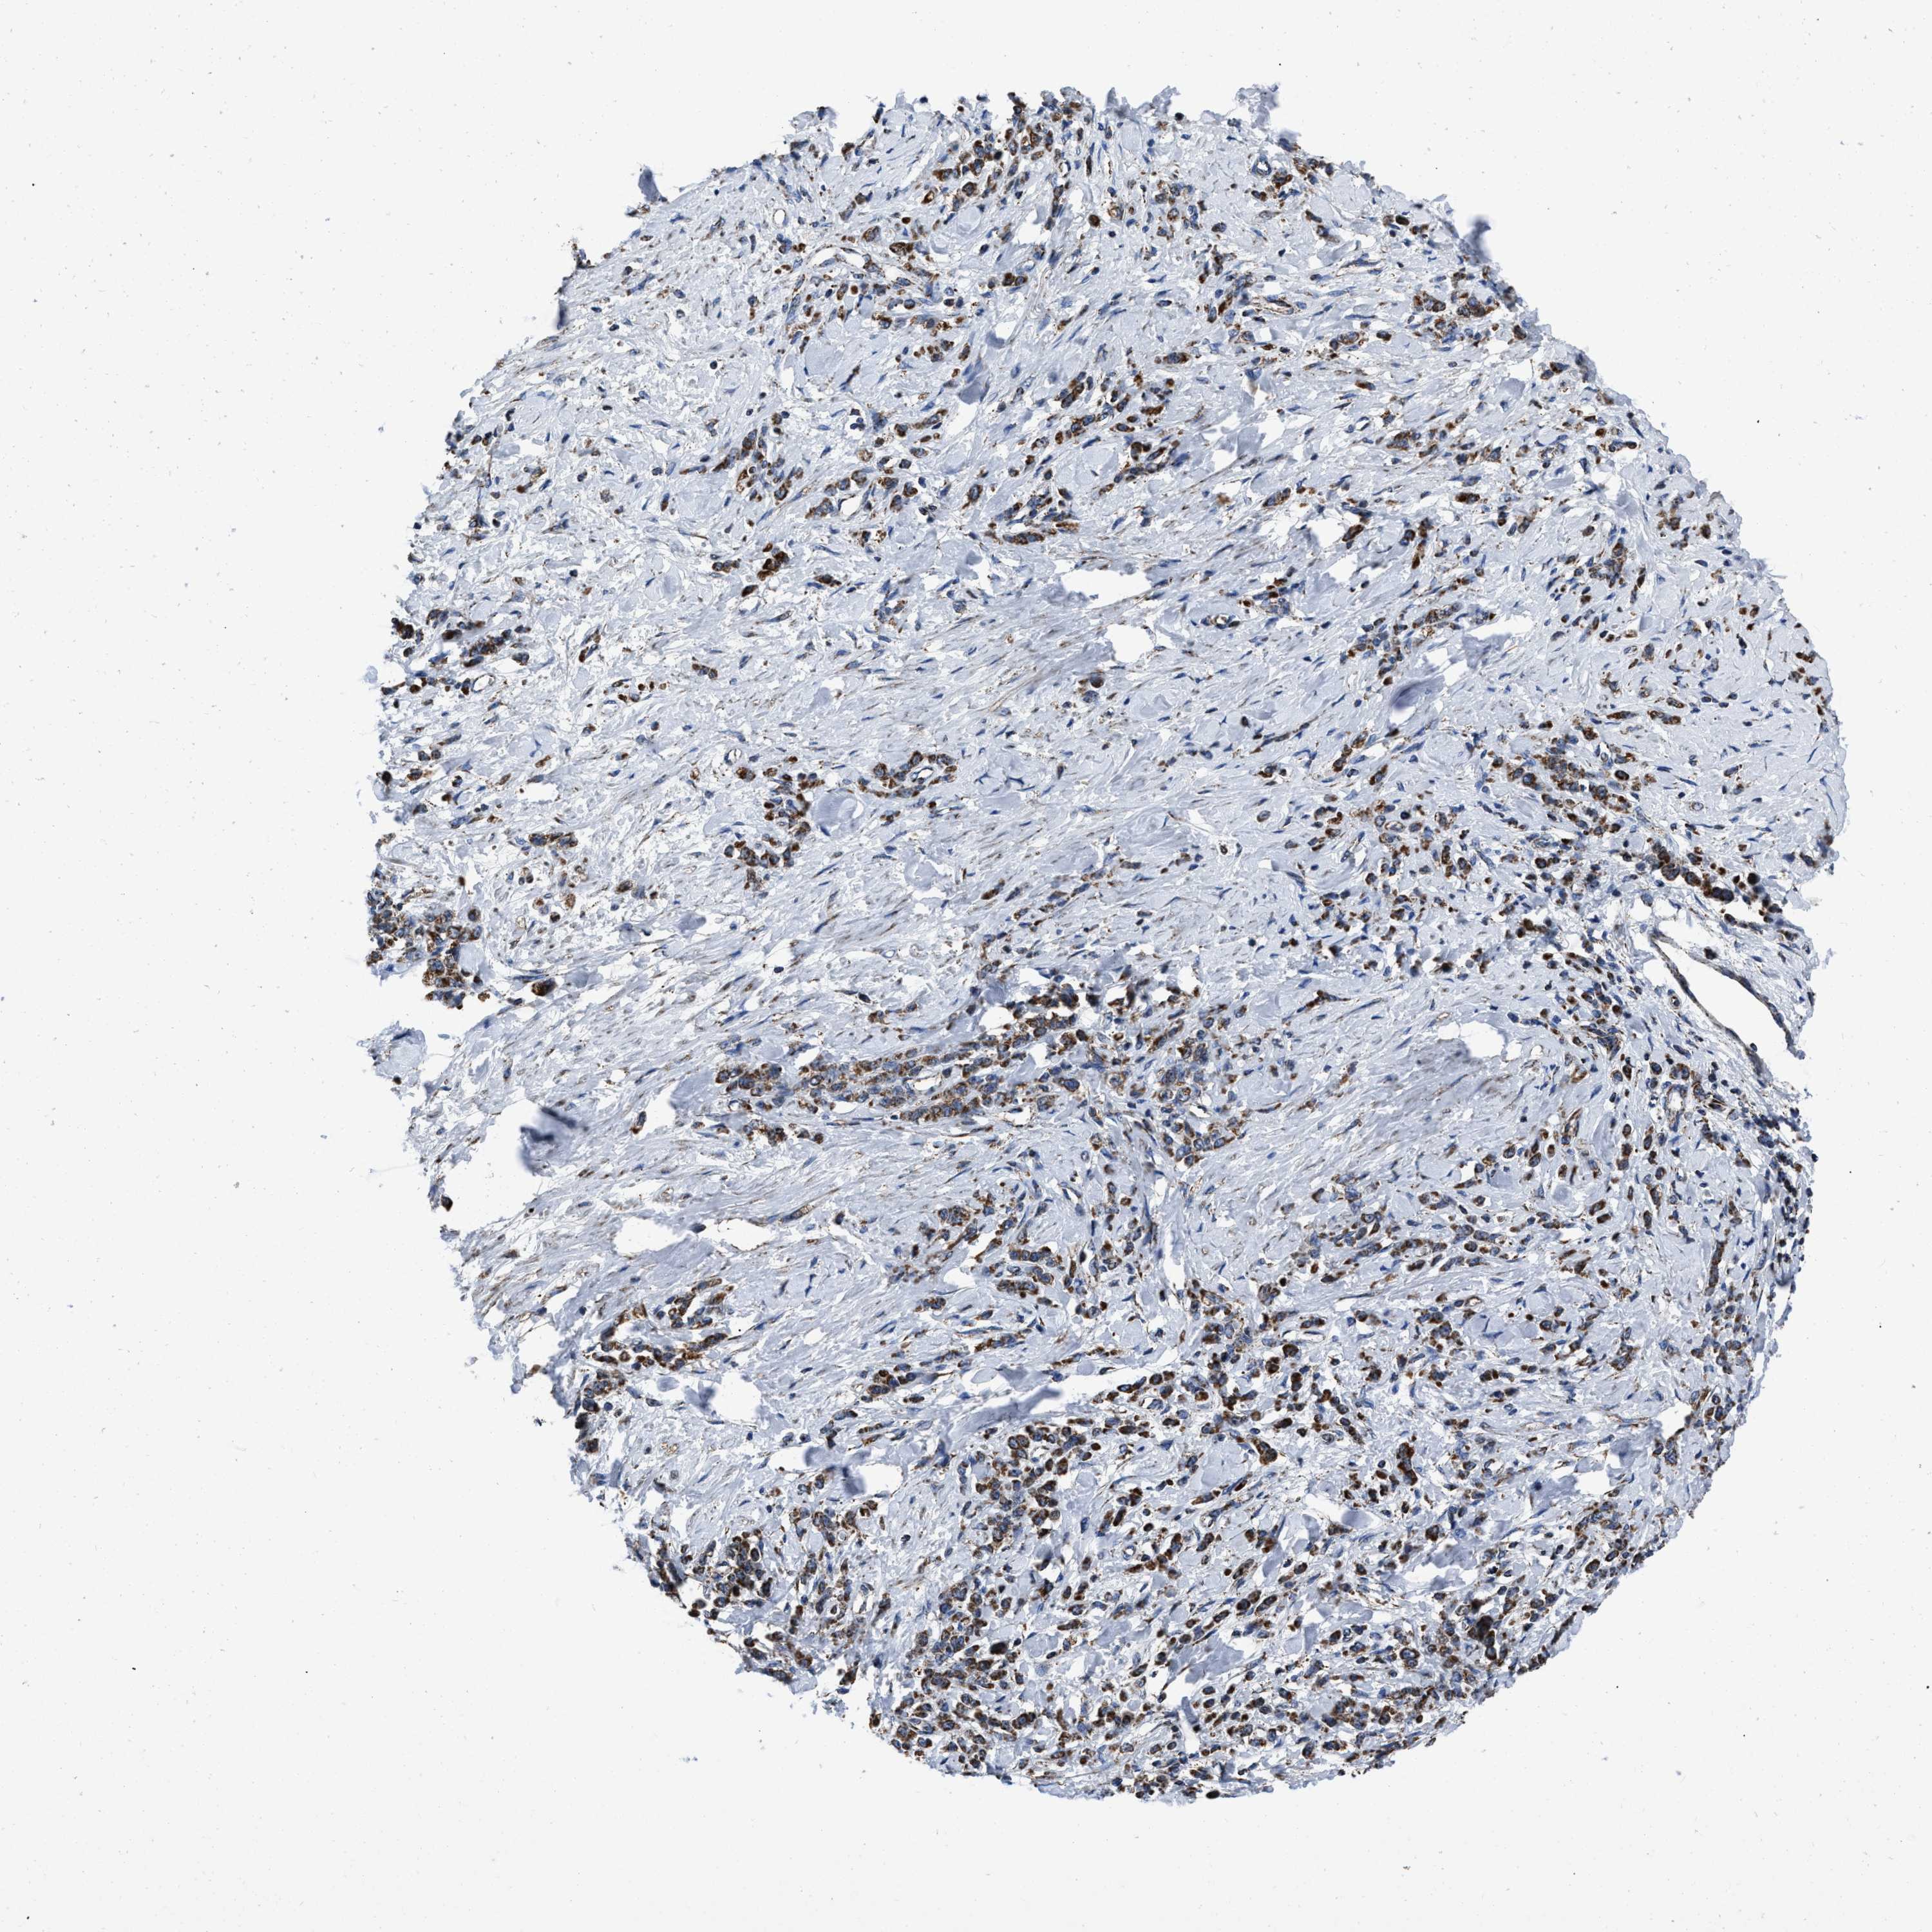

STOMACH CANCER - Protein expressioni

A mouse-over function shows sample information and annotation data. Click on an image to view it in a full screen mode. Samples can be filtered based on level of antibody staining by selecting one or several of the following categories: high, medium, low and not detected. The assay and annotation is described here.

Antibody stainingi

Antibody staining in the annotated cell types in the current human tissue is reported as not detected, low, medium, or high, based on conventional immunohistochemistry profiling in selected tissues. This score is based on the combination of the staining intensity and fraction of stained cells.

Each image is clickable and will lead to virtual microscopy that enables deeper exploration of all samples and also displays staining intensity scores, fraction scores and subcellular localization as well as patient and tissue information for each sample.

Antibody HPA018893

Staining

High

Medium

Low

Not detected

Intensity

Strong

Moderate

Weak

Negative

Quantity

>75%

75%-25%

<25%

None

Location

Nuclear

Cytoplasmic/membranous

Cytoplasmic/membranous,nuclear

Adenocarcinoma, NOS